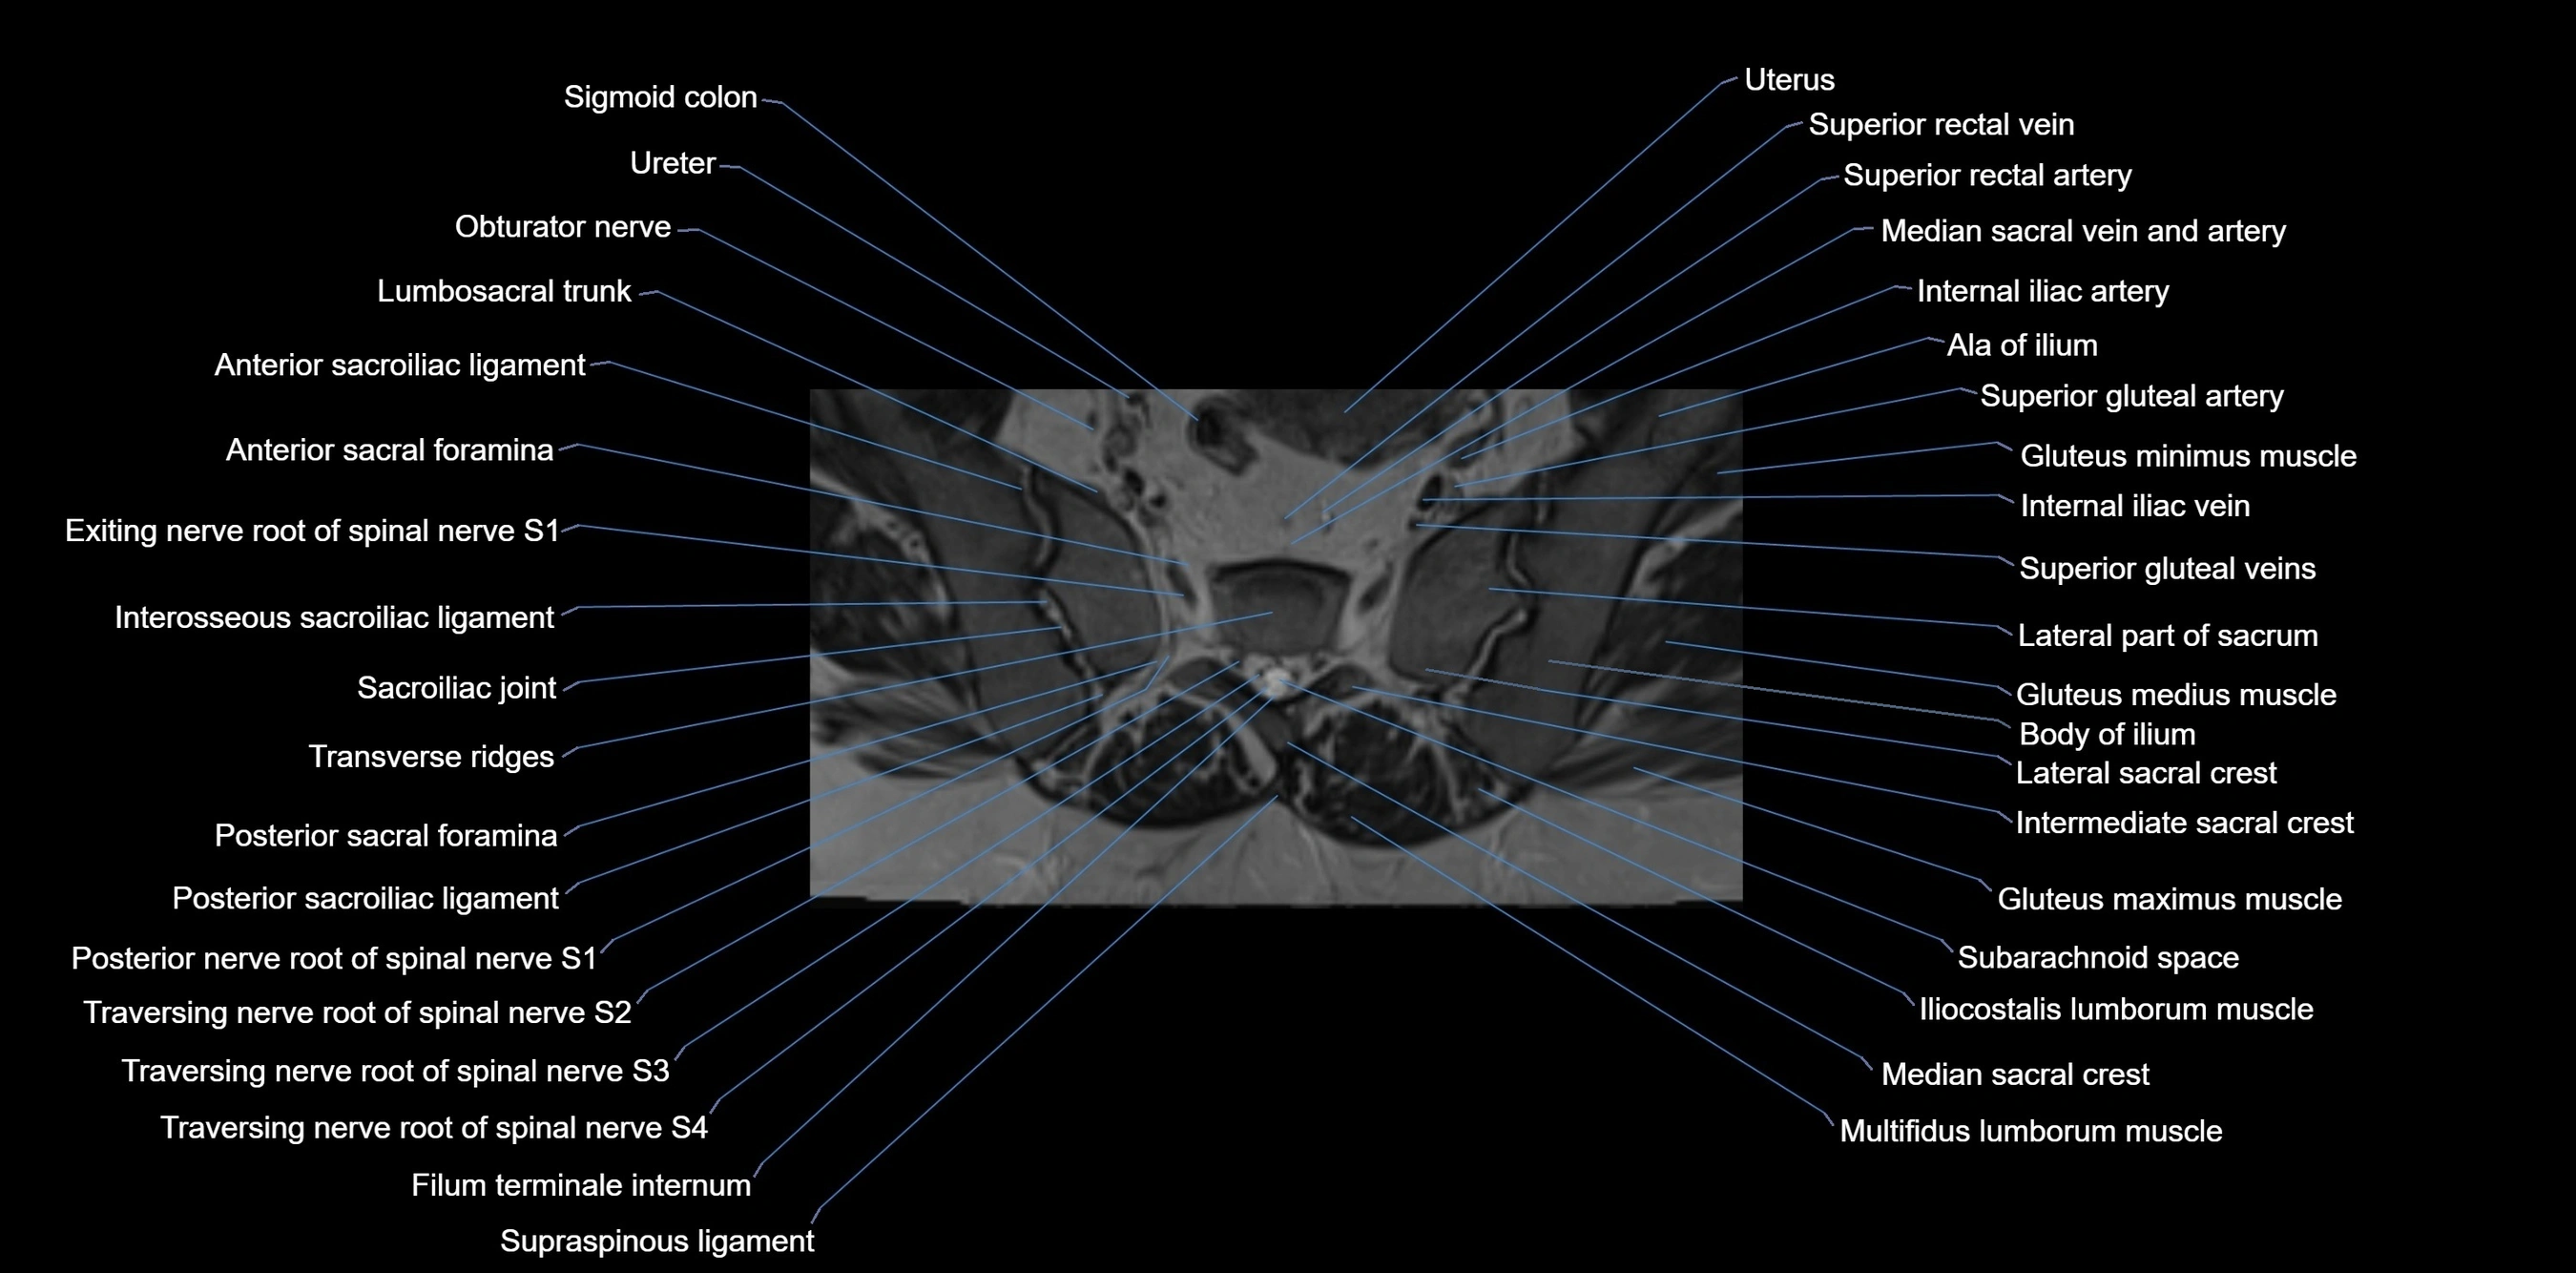

MRI Appearance

T1-weighted images:

• Cortical bone appears very low signal (dark); marrow shows intermediate signal

• Iliac fossa fat is bright against low-signal cortex

T2-weighted images:

• Cortical bone remains dark

• Marrow signal varies depending on fat content; edema or tumor shows hyperintensity

STIR:

• Suppresses fat, making bone marrow edema, fractures, or infiltrative lesions appear bright

• Excellent for trauma, sacroiliitis, and metastatic evaluation

T1 Fat-Saturated (Pre-contrast):

• Marrow: intermediate signal, fat suppressed

• Useful for detecting subtle marrow abnormalities adjacent to iliac cortex

T1 Fat-Saturated Post-Contrast (Gadolinium):

• Enhances vascularized structures, marrow pathology, tumors, and inflammatory changes

• Highlights soft tissue or bone invasion in pelvic neoplasms

MRI Non-Contrast 3D Imaging:

• Provides 3D morphology of iliac wing, crest, and articulations

• Used in preoperative planning for pelvic surgery and trauma reconstruction